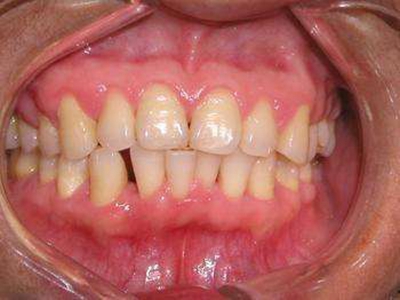

慢性龈炎又称边缘性龈炎或单纯性龈炎,主要表现为游离龈和龈乳头因炎性水肿,而变为鲜红或暗红色,龈缘变厚,龈乳头圆钝肥大。慢性龈炎的患病率高,治愈后仍可复发,部分患者可发展成为牙周炎。

慢性龈炎的病损部位一般局限于游离龈和龈乳头,以前牙区为主,尤其以下前牙区最为显著,患者常因刷牙或咬硬物时牙龈出血而就诊。游离龈和龈乳头颜色变为鲜红或暗红色,病变较重时炎性充血可波及附着龈。龈缘变厚,龈乳头圆钝肥大,可增生呈球状,覆盖牙面。牙龈松软脆弱,缺乏弹性。

当牙龈以增生性反应为主时,龈缘和龈乳头呈坚韧的实质性肥大,质地较硬而有弹性。龈沟液量增多,还可能出现龈沟溢脓现象。